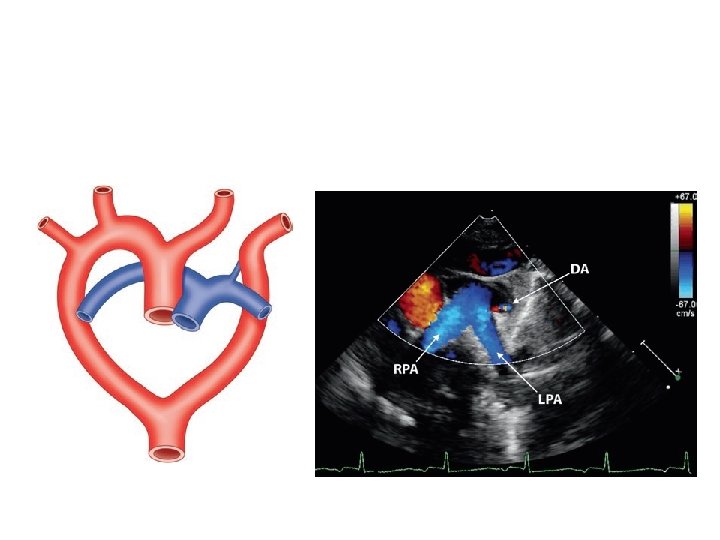

Pulmonary artery sling

• LPA arises as a branch of RPA • LPA courses in a position cephalad to right mainstem bronchus; between trachea & esophagus • Forms a "sling" and partially surrounds lower trachea • a/w tracheal stenosis • ONLY condition where a major vessel passes b/w trachea & esophagus